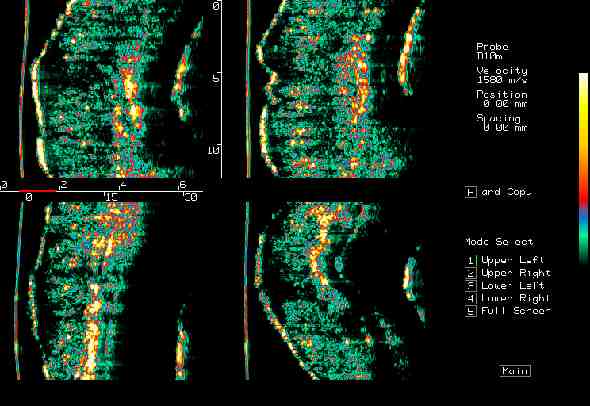

| Tumors |  BCC on the ear |

BCC, various sites |